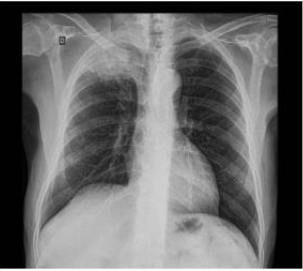

Paciente, sexo masculino, 65 anos de idade, hipertenso e tabagista 60 anos/maço, vem encaminhado da UBS por apresentar, há 3 meses, tosse seca, pletora facial e edema de membros superiores. Relata ainda 3 episódios sincopais no último mês, após acessos de tosse. Ao exame físico, apresenta bom estado geral, pletórico, turgência jugular bilateral. MVF. BRNF em 2 tempos. Abdome sem alterações. Edema de membros superiores 2+/4+. TC de crânio demonstra lesão expansiva intracraniana. A radiografia de tórax apresenta a imagem a seguir. De acordo com o quadro descrito, cite um achado da radiografia de tórax.